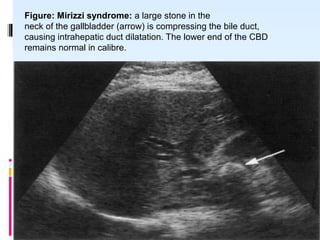

Figure: Mirizzi syndrome: a large stone in the

neck of the gallbladder (arrow) is compressing the bile duct,

causing intrahepatic duct dilatation. The lower end of the CBD

remains normal in calibre.